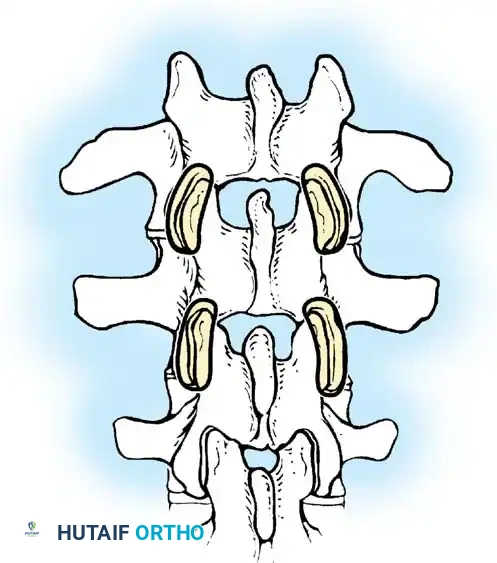

The Moe Technique (Lumbar Spine)

In the lumbar spine, the facet joints are oriented in a more sagittal plane, necessitating a modified approach.

Fig. 38-27: The Moe technique adapted for lumbar facet fusion, addressing the sagittal orientation of the joints.

- Utilize a small osteotome or a needle-nose rongeur to resect the adjoining joint surfaces.

- This creates a distinct rectangular defect within the sagittally oriented joint space.

- Pack this defect forcefully with cancellous bone graft.

- Proceed to decorticate the entire exposed posterior elements (laminae and transverse processes) using Cobb gouges, always directing force away from the spinal canal.